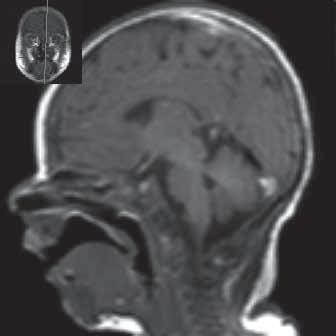

Obr. I.1.1a Fyziologické změny v závislosti na věku baze lební a corpus callosum, nízká intenzita signálu baze lební a klivu, respektive celé baze lební (červená kostní dřeň) v 1 měsíci života

Obr. I.1.1b Fyziologické změny v závislosti na věku baze lební a corpus callosum, zvýšený signál v crista gali a processus nasalis os frontale (počínající tvorba žluté kostní dřeně) v 1 roce života (šipka)